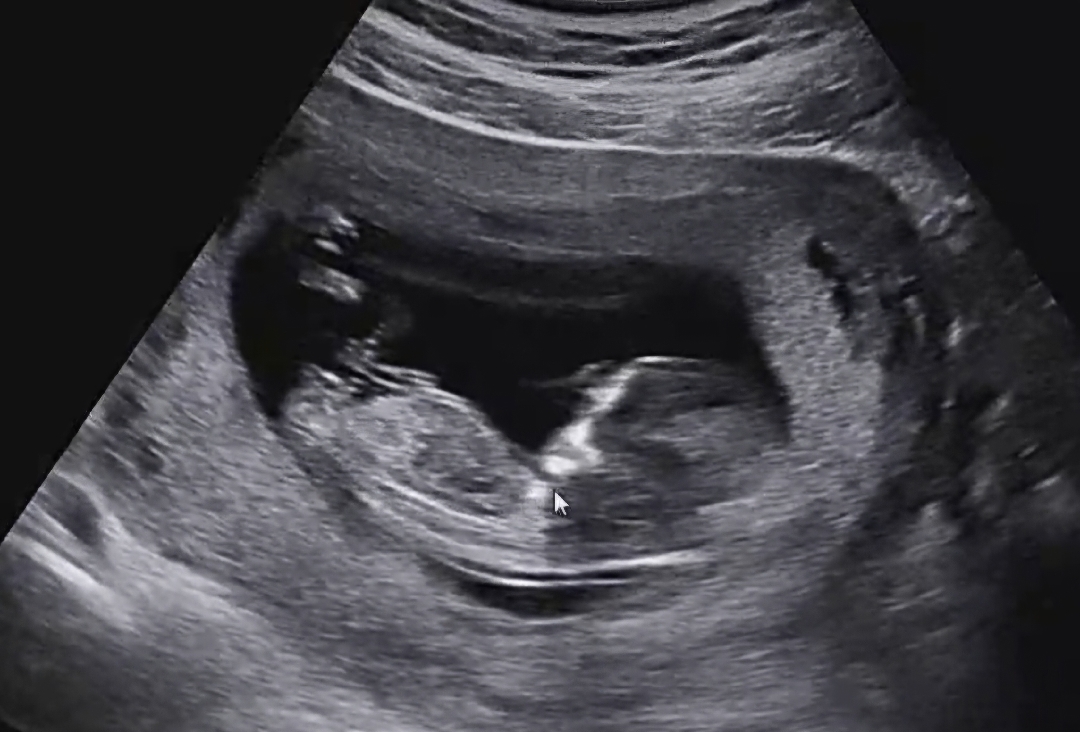

12주 2일 입니다. 걱정 반 설렘 반으로 검사와 초음파를 봤습니다. 무사히 마치고 나니 궁금증이 사악 ! 아들인지 딸인지 고수 분들 한 번 봐주세요.